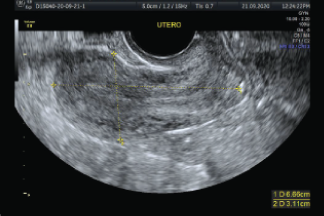

Es un procedimiento de ultrasonido transvaginal, generalmente se realiza primero para observar el endometrio, o las paredes del útero, incluyendo su grosor y toda anormalidad ovárica relacionada.

Es un procedimiento relativamente breve que ofrece una excelente visión del útero y las paredes del endometrio.

Muchas anormalidades uterinas que no se pueden observar de manera adecuada con un ultrasonido transvaginal de rutina se pueden observar en detalle con la histerosonografía.